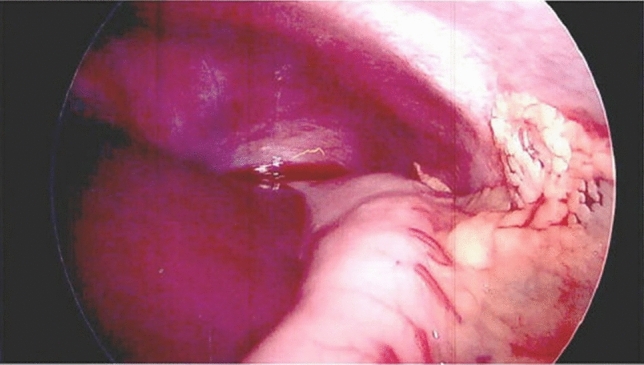

Methods and procedures: An 81-year-old Caucasian female was admitted to the emergency room with a complaint of 24-h epigastric pain, associated with nausea. She had history of a laparoscopic reduction of the foramen of Winslow internal hernia in our institution. CT scan of her abdomen showed a lesser sac internal hernia with an incarcerated colon and underwent a laparoscopic repair with a flap of falciform ligament and laparoscopic cecopexy. The surgery was successful.

Results: Foramen of Winslow hernias, a rare type of internal hernia. Internal hernias have an incidence rate of less than one percent, with Foramen of Winslow hernias accounting for only 8% of all internal hernias. The case at hand involves an 81-year-old Caucasian women who described a prior history of hypertension and a past laparoscopic reduction of the Foramen of Winslow internal hernia in the past. She had complaints of 24-h epigastric pain associated with nausea. She underwent a CT scan of her abdomen which revealed a lesser sac internal hernia with an incarcerated colon and was taken to the operating room where her Foramen of Winslow internal hernia was repaired laparoscopically using a flap of falciform ligament. The hernia contents included the ascending colon and ileum and were viable. A laparoscopic cecopexy and a flap of falciform ligament were done. The surgery was successful.